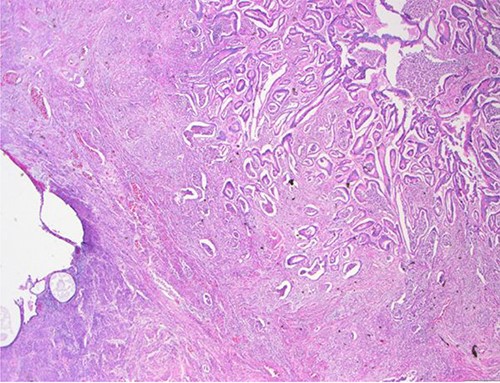

The definitive pathological report revealed adenocarcinoma metastases with morphology and immunophenotype compatible with an intestinal origin, both in splenic parenchyma and in uterine myometrium (see Figs 1–8).

Surgical specimen: splenectomy; macroscopically, neoplastic retraction of the splenic capsule corresponding with a nodular, well-circumscribed, whitish neoplasm, 45 mm in diameter; parenchymatous resection margins are intact.

Surgical specimen: splenectomy; microscopy, HE; spleen parenchyma infiltrated by well-formed neoplastic glandular structures composed of cells with ‘pencillated’ and atypical nuclei, with nucleoli, apoptosis and mitotic figures, consistent with an intestinal origin (metastatic colorectal adenocarcinoma).

Surgical specimen: splenectomy; microscopy, HE; spleen parenchyma infiltrated by well-formed neoplastic glandular structures composed of cells with ‘pencillated’ and atypical nuclei, with nucleoli, apoptosis, and mitotic figures, consistent with an intestinal origin (metastatic colorectal adenocarcinoma).